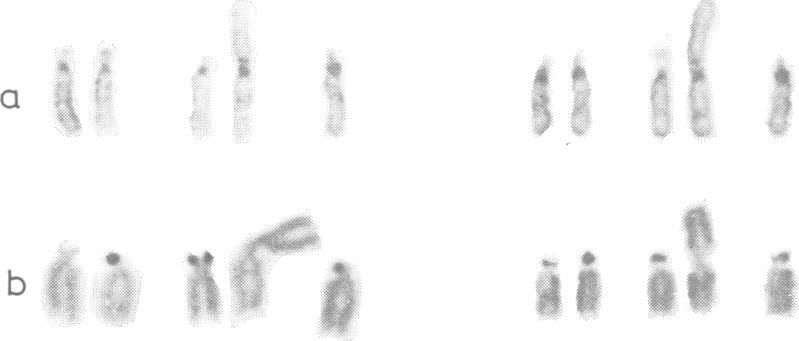

A case of trisomy 14q mosaicism is described and compared with three other similar reported cases. The clinical picture is characterised by severe developmental retardation, failure to thrive, and somatic abnormalities including skeletal asymmetry, high arched or cleft palate, and low set dysplastic ears. The present chromosome imbalance probably resulted from dissociation of a balanced 14q15q translocation with subsequent formation of a 14q isochromosome.

本文描述了一例14号染色体长臂嵌合体病例,并与其他三例已报道的类似病例进行了比较。临床表现为严重发育迟缓、生长发育不良以及包括骨骼不对称、高拱腭或腭裂、低位发育不良耳在内的躯体异常。目前的染色体失衡可能是由一个平衡的14号染色体长臂与15号染色体长臂易位解离,随后形成一条14号染色体长臂等臂染色体所致。